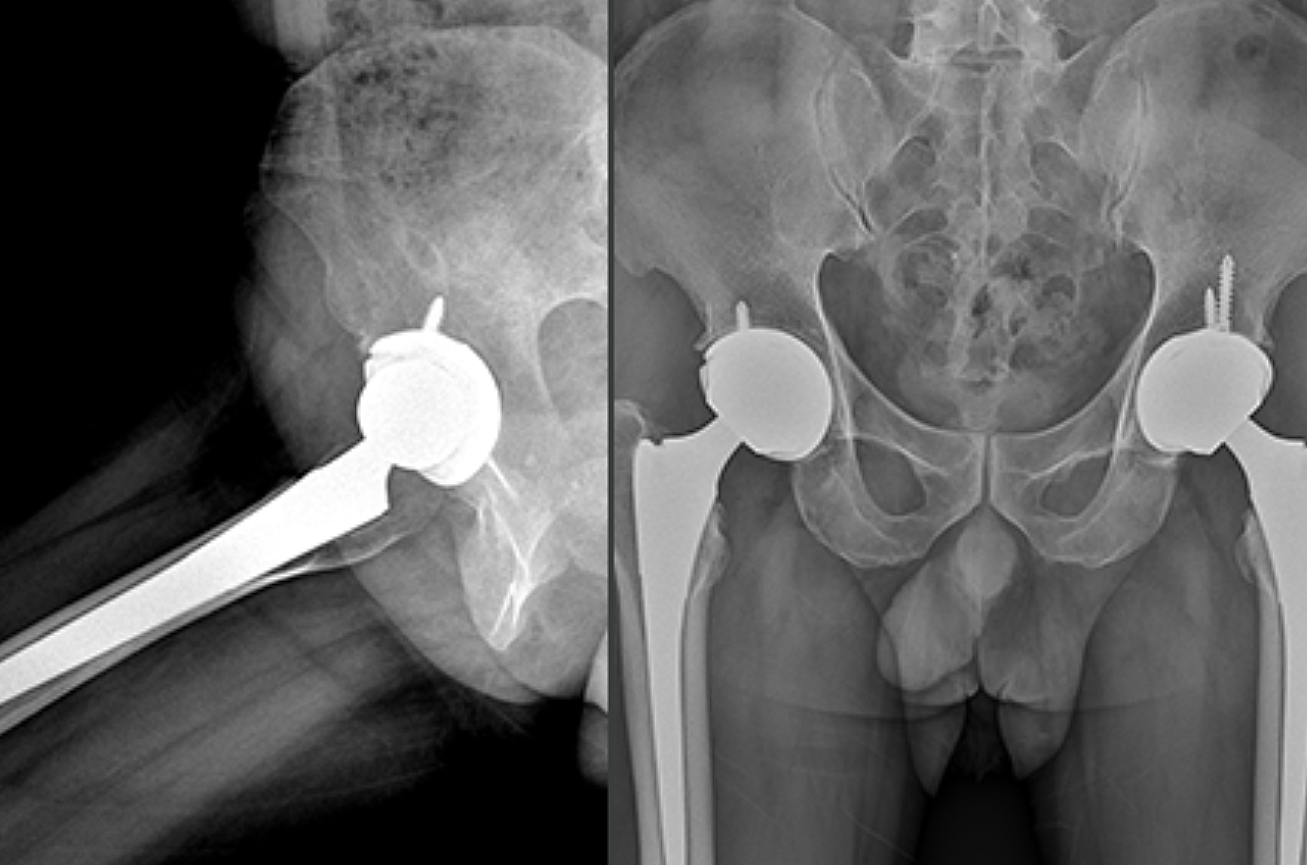

우리나라에서 발생하는 고관절 통증 증상의 가장 큰비중(70%)을 차지하는 대퇴골두 무혈성 괴사는특히 30~50대 젊은 남성에서 많이 발생하는 것으로 알려져 있습니다. 이 질환은 고관절의 기능을 완전히 잃게 할수 있어 주의가 필요합니다.

뚜렷한 원인은 밝혀지지 않았지만, 과다한 음주가 골 괴사의 위험을 높이는 가장 큰 원인입니다. 형외과 전문의는 “대퇴골두 무혈성 괴사는 여성보다는 남성에게서 많이 나타나고 환자의 60%는 양쪽 고관절 통증 증상에 모두 나타난다”며 “발병 요인 중 한국 남성들의 음주 습관이 큰 원인으로 꼽히고 있습니다. 자주 술을 마시게 되면 혈액에 콜레스테롤과 지방 등이 쌓이게 되고 이것이 혈관을 수축시키는데, 이때 혈압이 증가하고 혈액이 응고되면서 혈액 순환을 방해하게 됩니다. 과음으로 인해 급성으로 진행돼 고관절 뼈가 주저 앉는 사례도 있어 조기에 치료받는 것이 중요합니다.

고관절 통증 증상은 조기에 발견하고 치료받는 것이 무엇보다 중요합니다. 고관절 손상이 심하지 않고 통증이 가볍다면 약물치료와 운동치료 등 보존적 치료를 통해 회복할 수 있습니다. 하지만 고관절 손상이 심하고 일상생활에 지장을 줄 만큼의 심한 고관절 통증 증상이 있는 경우라면 괴사된 관절을 제거하고 인공관절을 삽입하는 고관절의 인공관절 치환술을 해야 합니다.